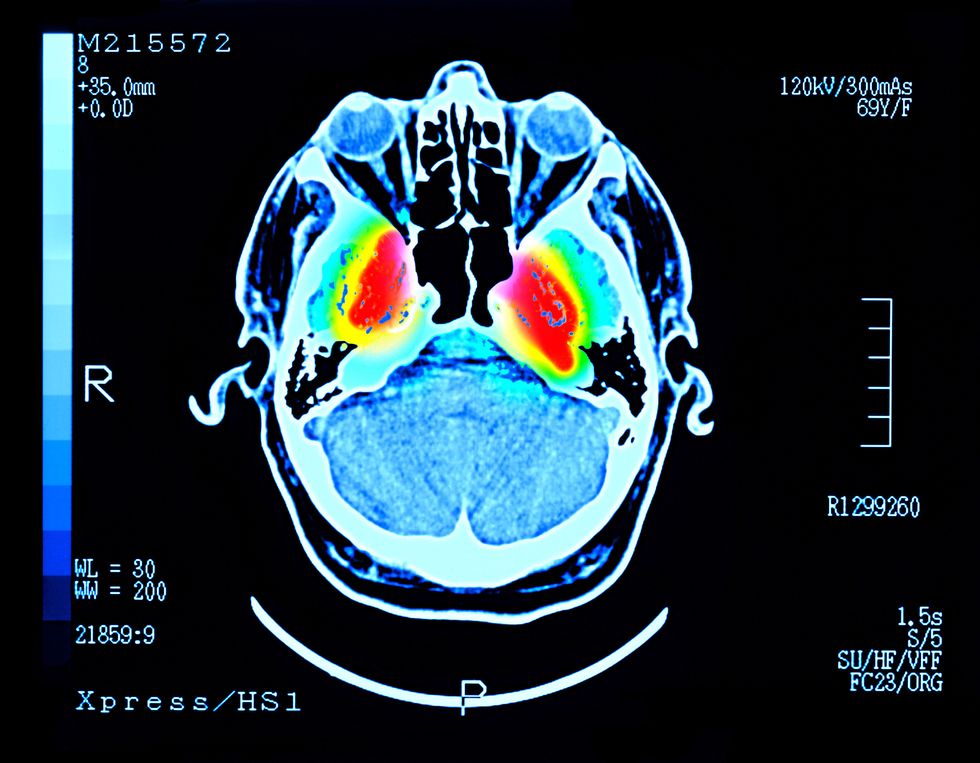

Blood tests were conducted at baseline after four weeks and eight weeks. Magnetic resonance spectroscopy imaging showed an 11 per cent increase in brain creatine levels after eight weeks.